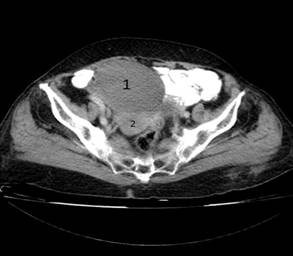

- Tomografía axial computadorizada (TAC) abdominal con doble contraste: en cortes a 5 mm se observó una masa tumoral a nivel de la fosa iliaca derecha que mide 89 x 78 mm, con densidades variables a predominio de las del rango de 50 a 70 UH y en el centro de 21 a 32 UH (imagen 1). La lesión captó el contraste intensamente. Comprimía y desplazaba el colon hacia arriba y a la izquierda, también, a la vejiga. Teniendo en cuenta las características de la lesión, se considera que se trata de un tumor sólido del ovario derecho.

IMAGEN 1. En las tomografías realizadas, tanto simple (izquierda) como contrastada (derecha), es posible observar la gran masa tumoral (1), que desplaza al útero (2) y a la vejiga (3)